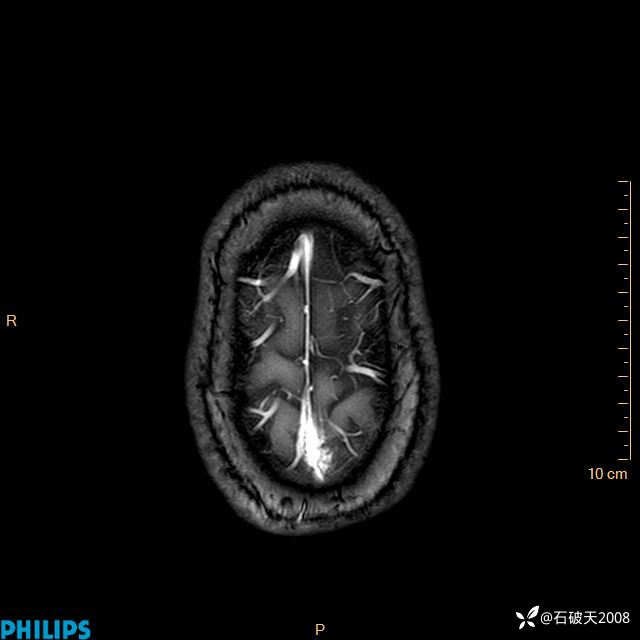

2024.2.21MR

增强轴位